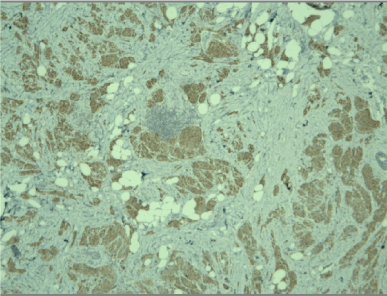

A frozen section was performed during surgery and the result was “invasive tumor, suspicious for malignancy”. Radical left mastectomy was performed with axillary lymph nodes dissection. The histological examination of the symptomatic lesion (11 mm) revealed a tumor, composed of nests of epitheloid tumor cells with monomorphous nuclei with occasional nucleoli, areas with spindle tumor cells in a fibrous background with hyaline change, areas with mature adipocytes. Peripheral nerves were surrounded by tumor nests (Figure 1). Scattered lymphocytic infiltrates were also found. PAS reaction revealed single positive granules in a few tumor cells (Figure 2). The described histological findings are observed in both mammary MFB and granular cell myoblastoma. Immunohistochemical analysis was performed. The tumor cells were positive for: S-100 protein (Figure 3), CD68 (Figure 4), Vimentin (Figure 5). The proliferative index detected with Ki67 is low (1-2%) (Figure 6). The tumor cells were negative for ER, PR and HER. The histological examination of the dissected lymph nodes revealed sinus histiocytosis, follicular hyperplasia and lipomatosis. Metastases were not found.

Figure 3. Positive cytoplasmic reaction for S-100 protein in tumor cells, x10